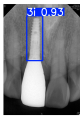

However, since the implant launched onto the market, dental treatment related to implant issues has become the everyday practice of dentists’ lives in clinics [10]. The design of the implants, from shape to surface coating, is different from brand to brand [11]. But it is inevitable to come into implant complications [12,13], such as screw fracture, healing abutment loss, etc., whether the clinician itself treats the implant or implant prosthesis. Different surface coatings [14,15] and threads of the implant design [16,17] may be easily identified in vitro. Moreover, once the implants are in vivo, the clinicians can only identify implant brands through radiography or the clinicians’ familiarity with the implant. If the clinicians are not familiar with the brands, then it is hard to tell which brand the implant is from in vivo. As the number of implant brands on the global market grows, it has become increasingly complex for clinicians to identify and familiarize themselves with all available implant systems accurately. 3i and Xive are two of the most widely used and clinically validated implant brands worldwide, with excellent long-term success rates [18] and reliable implant-abutment connection designs [19]. Therefore, we strategically focused on 3i and Xive implants in this study to ensure clinical relevance and practical significance. Concentrating on these two brands allows our model to address many real-world clinical cases and enhances its applicability in everyday dental practice. Clinicians will likely encounter both implant brands due to their widespread use in global dental clinics [20]. Moreover, as the implant’s screwdrivers differ from brand to brand, the identification of implant brands is very important to clinicians and patients. The marginal accuracy of the implant-abutment connection may vary due to misidentification and lead to unknown clinical problems [21,22]. The PA imaging results of two implant brands of different types at different resolutions (R) are shown in Figure 1. These two commonly used implant brands exhibit highly similar characteristics, with the most apparent difference being the variation in implant threading patterns. However, this distinction is not easily discernible for PA datasets.

Figure 1.

Imaging of two implant brands at different resolutions.